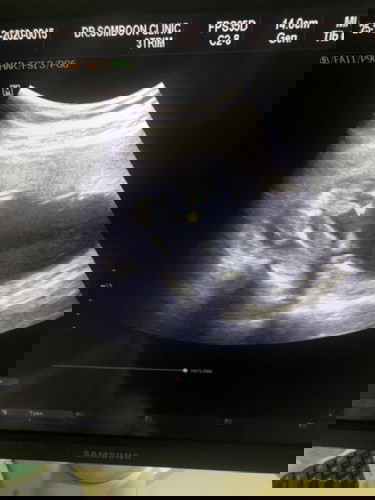

สอบถามภาพอัลตร้าซาวด์

แบบนี้เพศชาย ชัวร์มั้ยค่ะ

ชัดมากค่ะ 😄